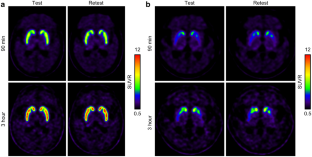

Fifteen ET (68.9 ± 6.6 years) and 10 PD patients (70.5 ± 6.3 years; Hoehn and Yahr stage, 2.3 ± 0.8) underwent two [18F]FP-CIT PET/CT scans with an interval of 48 ± 7 day. For both the test and retest studies, standardized uptake value ratios were estimated for 90-min and 3-h acquisitions for the caudate, anterior putamen, and posterior putamen using T1-MRI-based normalization (automatic) and fixed-VOI (manual) methods, with the occipital lobe as a reference. Reproducibility was evaluated by the bias, variability, percent test–retest, within-subject coefficient of variation, repeatability coefficient, and intraclass correlation coefficient (ICC).

Reproducibility was excellent, with low variability (ET: 6.99–8.02%, PD: 3.51–6.94%) and high reliability (ICC; ET: 0.88–0.96, PD: 0.98–0.99). The ET group showed higher variability and lower ICCs than the PD group. The variability in the 90-min images (ET: 7.85–8.59%, PD: 1.52–2.75%) was comparable to that in the 3-h images (ET: 6.99–8.02%, PD: 3.51–6.94%). There were no differences in variability among the subregions in the ET group. In the PD group, the variability was high in the posterior putamen (automatic method: 6.94%, manual method: 11.80%). The test–retest variability and ICCs were similar for the manual and automatic methods.